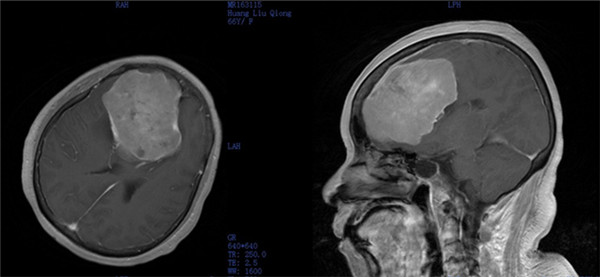

近日,一附院外六科(神经外科)成功进行1例颅底巨大廉旁脑膜瘤开颅显微切除术,肿瘤大小达9.2cm×7.5cm×7.9cm,接近一成年男子拳头大小,在广西区内实属罕见。

术前影像